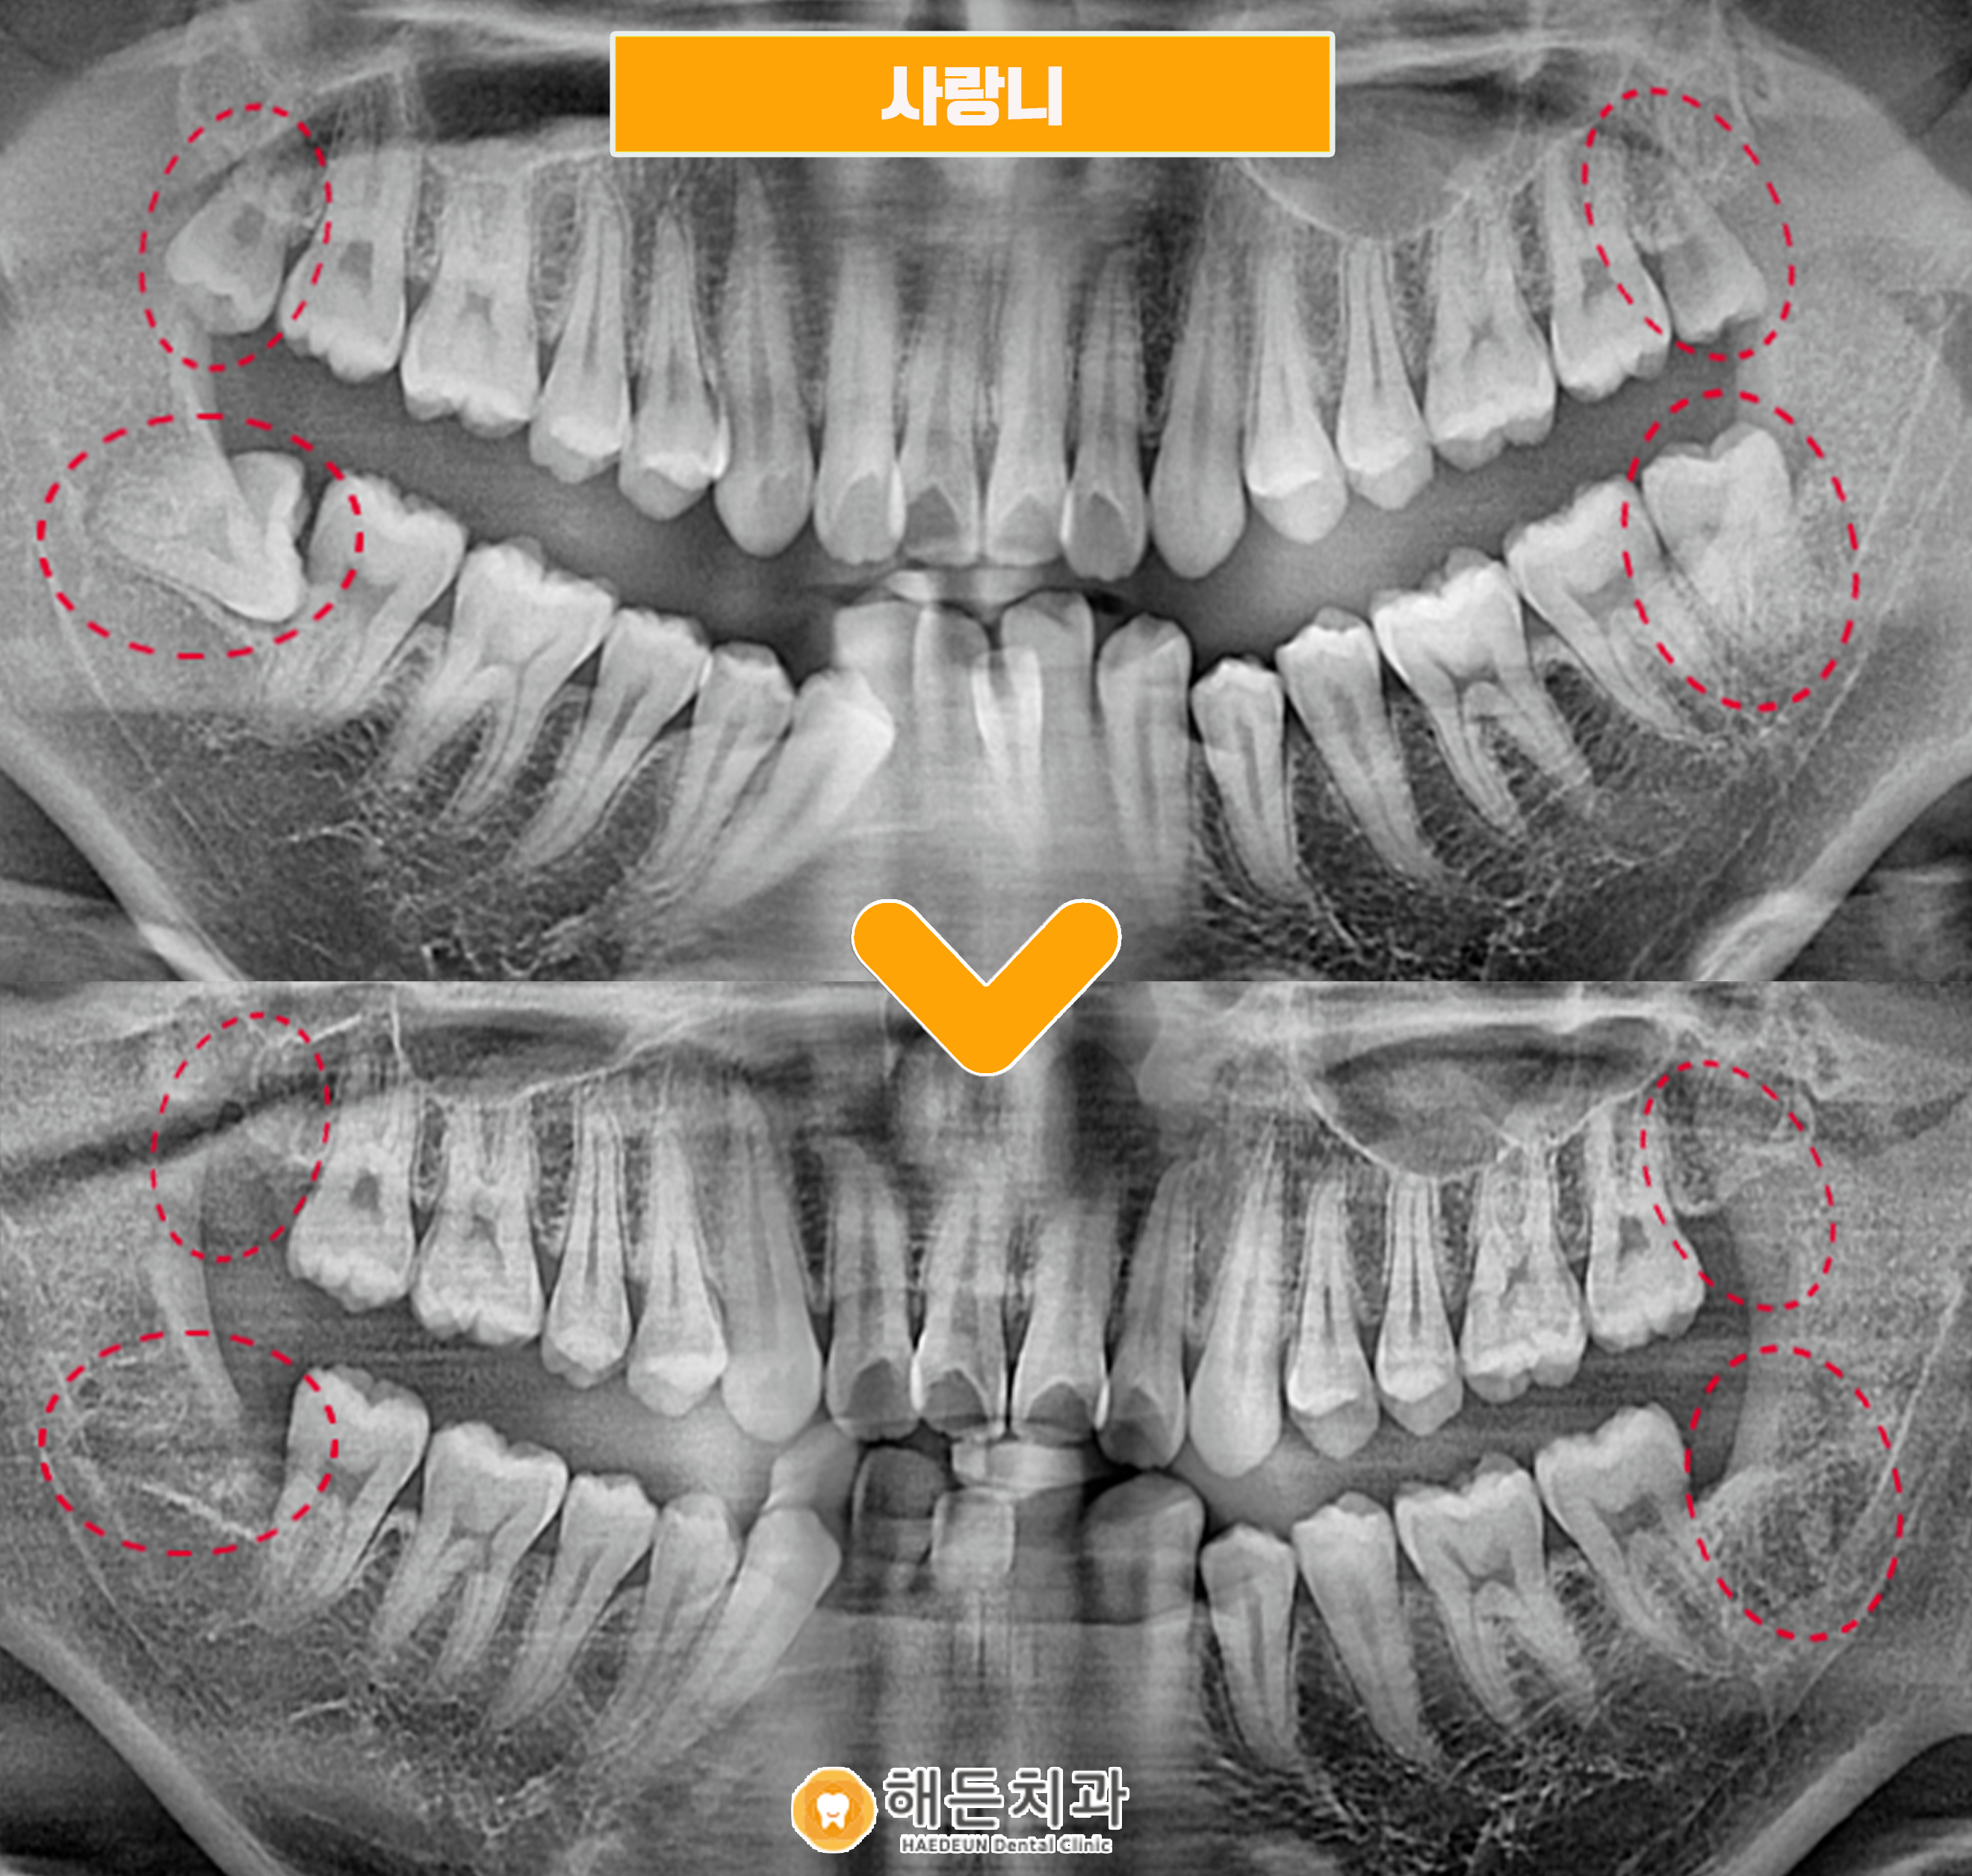

파노라마 사진을 촬영하여 확인해 보았더니 사랑니가 위아래 모두 맹출이 되어있었으며, 오른쪽 아래를 제외한 나머지 3개는 비교적 올바른 방향으로 맹출이 되어있었는데요.

이 경우 계속 방치하게 되면 차후 충치가 생기거나 주변 치아에도 영향을 끼칠 수가 있기 때문에, 위생적인 구강 관리를 위해서는 발치하는 것이 좋다고 판단이 되어 환.자분과 꼼꼼한 상.담을 진행한 후에 사랑니 4개를 모두 발치하기로 계획하였습니다.

4개 모두 남은 뿌리 없이 깔끔하게 사랑니발치를 도와드렸습니다. ✌

🦷 전 >후 🦷